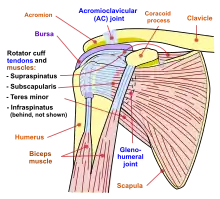

Diagram of the human shoulder joint, front view

Diagram of the human shoulder joint, front view Diagram of the human shoulder joint, back view